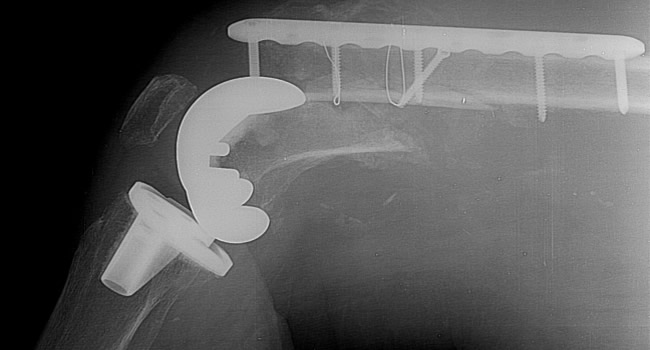

Οι ακτινογραφίες πραγματοποιούνται με πλήρως ψηφιακό εξοπλισμό και όχι ψηφιοποιημενο από έμπειρους Τεχνολόγους – Ακτινολόγους με άδεια ασκήσεως Επαγγέλματος.

Ο πιο σύγχρονος φορητός Ακτινολογικός εξοπλισμός πλήρως ψηφιακής απεικόνισης (DR) σε μια κινητή ακτινολογική μονάδα, μπορεί να επισκεφθεί τον ασθενή οπουδήποτε στην περιοχή της Θεσσαλονίκης και των περιχώρων και να σταλεί, αν ο ασθενής το επιθυμεί, η γνωματευμένη ακτινογραφία ηλεκτρονικά μέσω διαδικτύου στον θεράποντα- παραπέμποντα ιατρό ο οποίος θα λάβει το αποτέλεσμα στο προσωπικό του υπολογιστή, tablet, Smartphone οπουδήποτε κι αν βρίσκεται.